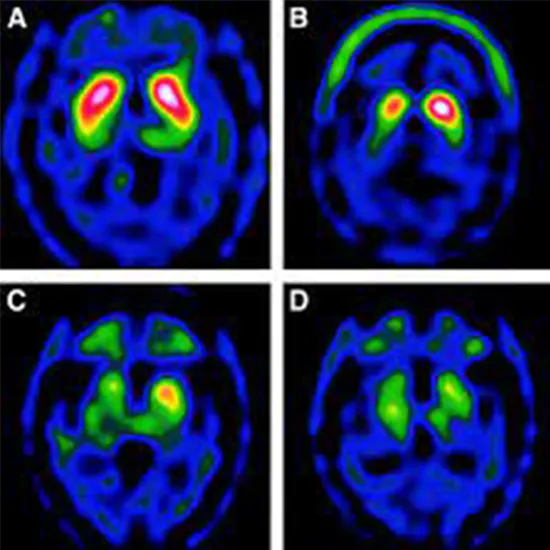

Tc-TRODAT, which binds to the dopamine transporter, could be used to image the dopaminergic system in Parkinson's disease diagnosis (PD). Parkinson's disease is divided into two types: late-onset Parkinson's disease (LOPD) and early-onset Parkinson's disease (EOPD) (EOPD).

You will be given a tracer, which is a radioactive medicine that labels the dopamine cells in your brain. This substance is detected by a specialized camera, which takes images of your brain to show the location and density of dopamine cells.